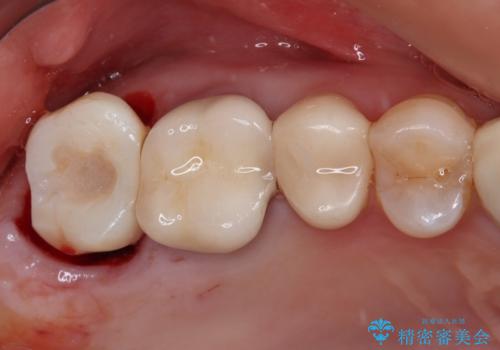

インプラントと骨の安定程度を測定したところ、十分な数値が得られたため、速やかに仮歯を装着して咬合回復をさせることができました。

抜歯を含めた外科処置を1回に抑えることができ、あっという間に治療を終えることができました。